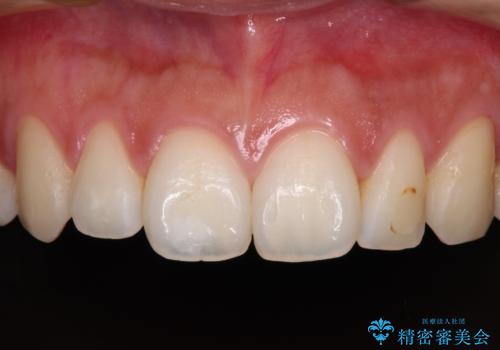

保険診療の黄ばんできた前歯をオールセラミッククラウンで自然な歯に

前歯の色が気になる【オールセラミッククラウン】